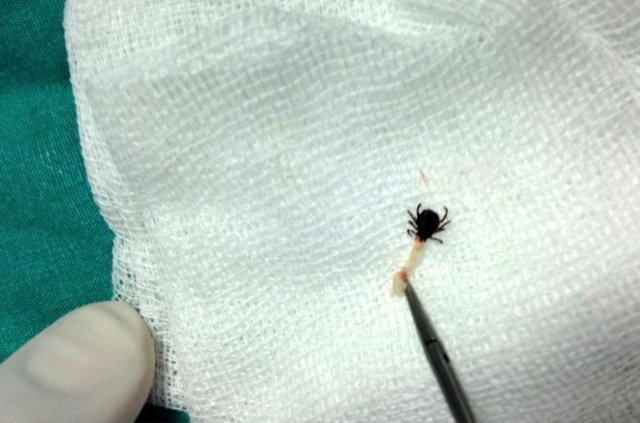

Serik İlçesi Devlet Hastanesi'nde yaşandı. Kulak ağrısı şikayeti ile hastanenin Kulak Burun Boğaz (KBB) polikliniğine giden 64 yaşındaki Fatma Türker'in yapılan muayenesinde, kulak zarına yakın bir bölgeye kene yapıştığı tespit edildi. KBB Uzmanı Op. Dr. Mustafa Altıntaş, kulak içerisinde sık karşılaşmadıkları keneyi görünce büyük şaşkınlık yaşadıklarını söyledi.

Serik'te hayvancılık ve çiftçilikle uğraşan hastanın 2- 3 gün önce özel bir sağlık kuruluşuna kulak ağrısı şikayeti ile başvurduğunu söyleyen Op. Dr. Altıntaş, "Gittiği doktor, kulağında iltihap olduğunu söylemiş. Kendisine ilaç vererek evine göndermiş. Tabi hastanın şikayetleri geçmeyince bu kez bize geldi. Yaptığımız muayenede kenenin kulak içine yapıştığını ve hala canlı olduğunu gördük. Özel bir teknikle kenenin tam ağzını yakalayarak, kulaktan çıkardık. Bölgede keneden kalma herhangi bir parça kalmamasına özellikle dikkat ettik" diye konuştu.